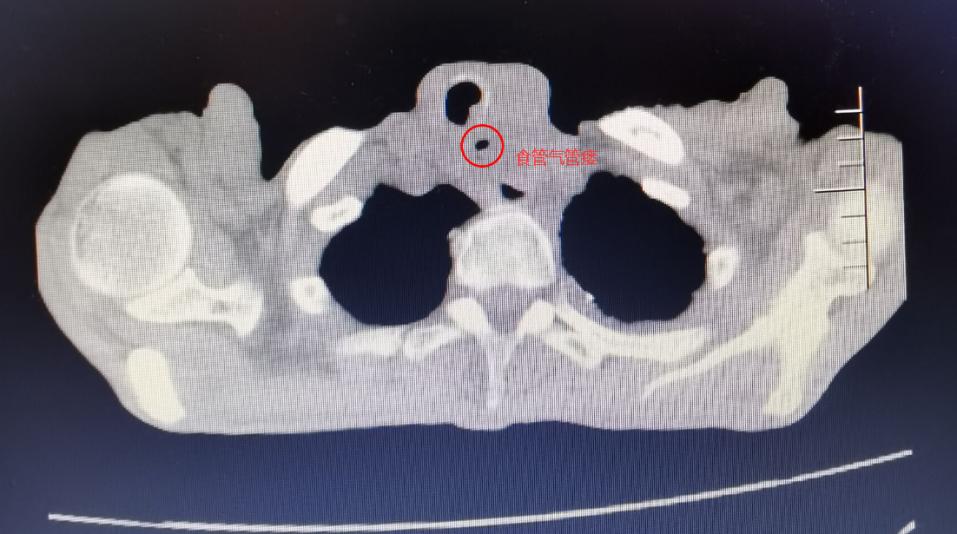

患者,男,70岁,食管癌合并食管气管瘘,咳嗽、咳痰伴呼吸困难,无法平躺入睡,每天坐立睡觉,生活质量较差,为得到进一步治疗,该患者到我院肿瘤介入科就诊。

住入肿瘤介入科后,检查发现患者为食管癌致食管气管瘘,患者已无法正常进食,出现气短、咳嗽、咳痰等症状,且因食管气管瘘口的存在,进食食物入肺部导致肺内感染。经肿瘤介入科团队会诊及与患者家属再三沟通后,决定给予患者“食管堵瘘”治疗,在做好充分准备后,介入科团队在DSA引导下行气管支气管支架置入术,术后造影提示瘘口得到有效封堵。患者生命及生活质量明显提高。

食管气管瘘